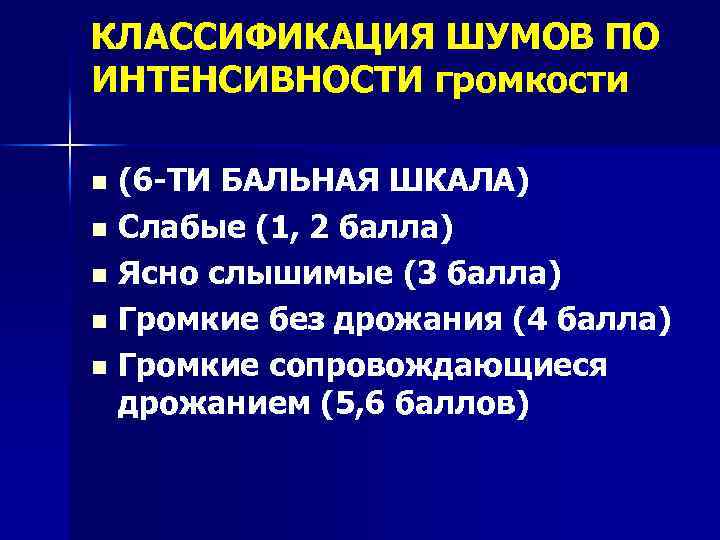

КЛАССИФИКАЦИЯ ШУМОВ ПО ИНТЕНСИВНОСТИ громкости (6 -ТИ БАЛЬНАЯ ШКАЛА) n Слабые (1, 2 балла) n Ясно слышимые (3 балла) n Громкие без дрожания (4 балла) n Громкие сопровождающиеся дрожанием (5, 6 баллов) n